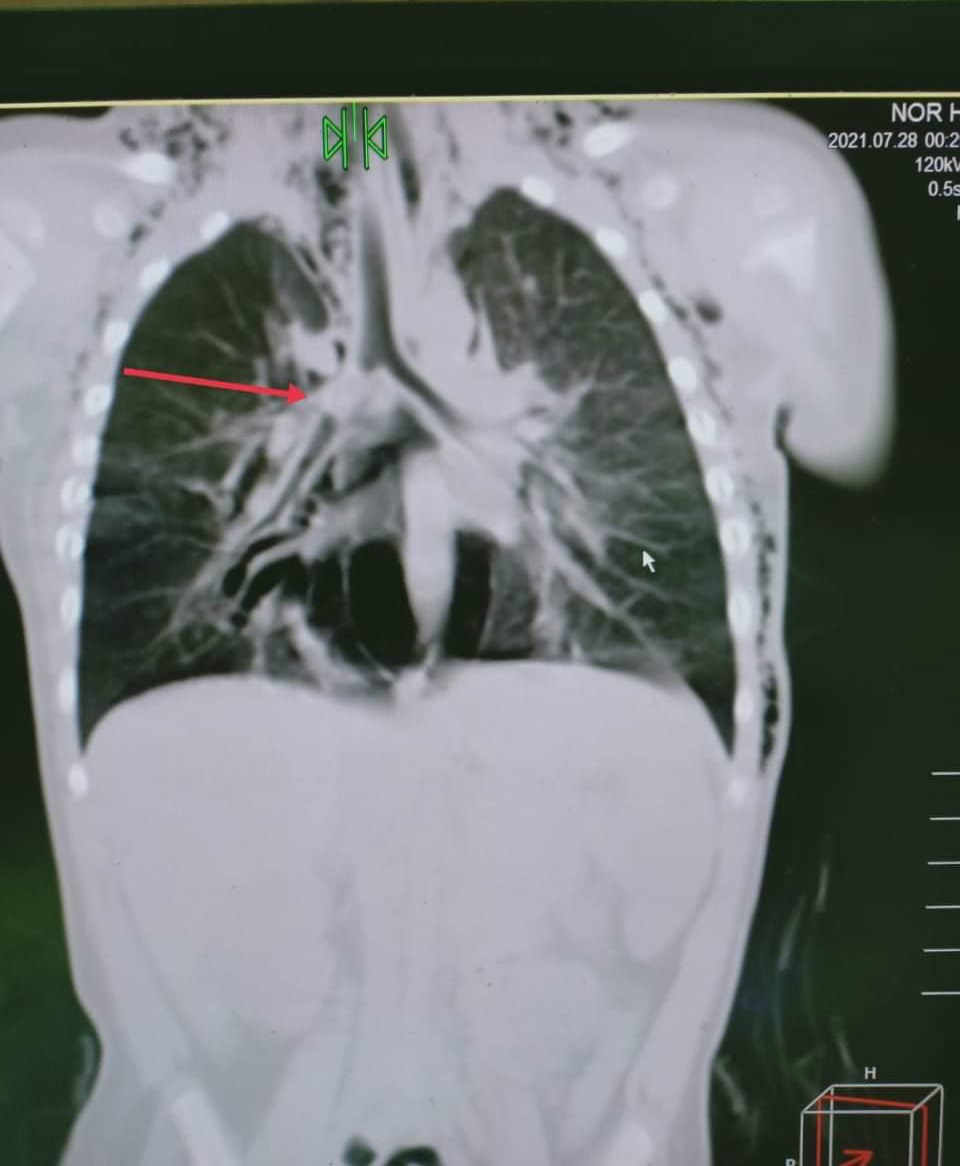

نجح الفريق الطبي بمستشفى الأطفال التخصصي بدمسنا بالبحيرة، والمكون من الدكتور محمد النجار، أخصائي الأنف والأذن، والدكتور أحمد الشرقاوي، أخصائي التخدير، في استخراج جسم غريب "حبة سوداني" من الرئة اليمنى لطفلة عمرها سنة.

وتم تشخيص وعلاج طفلة تعاني من استنشاق جسم غريب، وتم تشخيص الحالة بمستشفى دمنهور التعليمي، وتم نقلها إلى مستشفى الأطفال التخصصي بدمسنا لعمل منظار قصبة هوائية وشعب هوائية، وتم استخراج الجسم الغريب بنجاح وإنقاذ الطفلة من الموت المحقق.